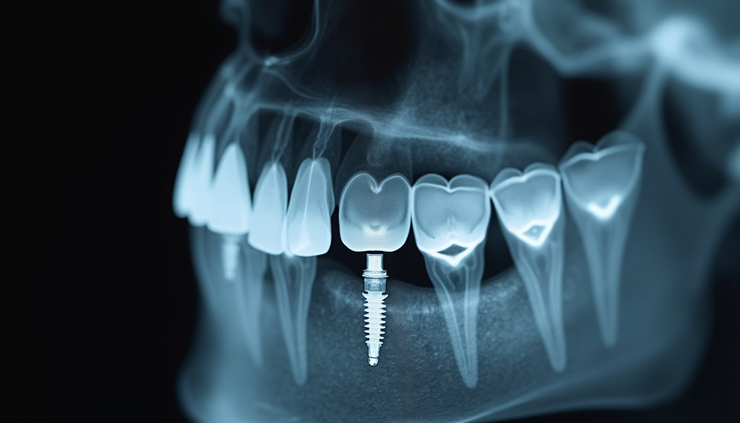

L'osteointegrazione è il processo biologico attraverso cui l'impianto si integra con l'osso mascellare o mandibolare. Questo passaggio è cruciale per la stabilità a lungo termine dell'impianto.

Dopo l'inserimento, l'osso inizia a crescere attorno alla superficie dell'impianto, fissandolo saldamente. Questo processo richiede generalmente da 3 a 6 mesi, a seconda delle condizioni individuali del paziente e della qualità dell'osso.

Eventuali radiografie per verificare l'integrazione ossea.